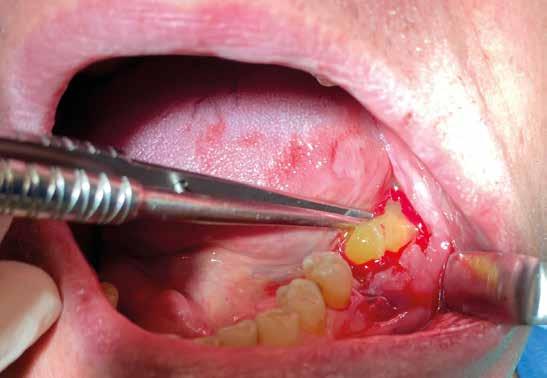

2. Estrazione dentaria (Figg. 3-6)

Estrazione di 3 elementi dentari complicata da frattura coronale di 2.4 e presenza di 2 corone protesiche unite su denti pluriradicolati. L’approccio deve prevedere la rimozione delle corone protesiche e la separazione delle radici, semplificando le manovre di estrazione e consentendo di risparmiare i tessuti molli pericoronali e prevenire la frattura

Il rispetto dei tessuti molli consente di ridurre i tempi di guarigione, sebbene a siti più ampi corrisponda un tempo di ripristino o maggiore. Il mantenimento delle corticali vestibolari, palatine e l’assenza di alveolite post-estrattiva riducono l’atrofia ossea.

FIG. 2 FIGG. 5,6: FIG. 5 FIG. 6 FIGG. 3,4: delle corticali ossee più sottili. FIG. 3 FIG. 4